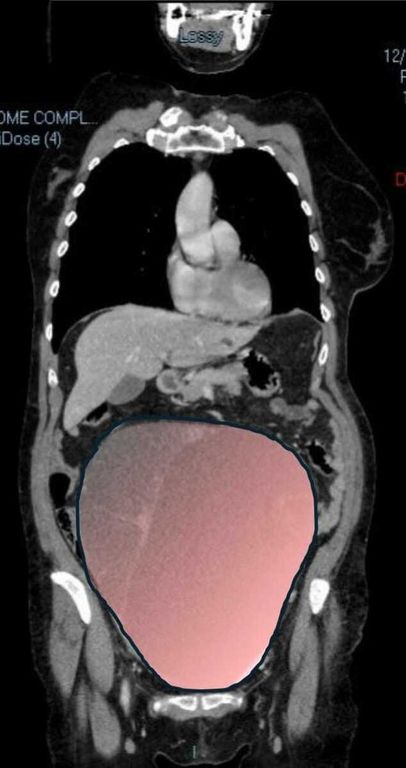

Per mesi la gigantesca cisti ovarica, con un diametro di circa 28 centimetri, è rimasta nascosta, senza dare segnali evidenti. La paziente non si era accorta di nulla. L’allarme è scattato quando la massa, associata alla presenza di una seconda neoplasia intestinale, ha iniziato a comprimere il colon, provocando sintomi acuti ed improvvisi fino ad una grave difficoltà intestinale non più ignorabile.

Fondamentale in questa fase il contributo della Radiologia dell'ospedale Sant’Anna, che fornisce l’imaging preoperatorio indispensabile per affrontare un quadro clinico di eccezionale complessità.

Durante l’intervento emerge tutta la gravità della situazione. La gigantesca neoplasia ovarica viene asportata: pesa circa 6 chilogrammi, con un volume paragonabile a quello di una gravidanza gemellare a termine. Ma non è l’unica minaccia. I sintomi più pericolosi sono legati alla sofferenza intestinale, che richiede un intervento immediato e coordinato di più specialisti.